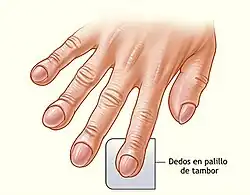

- Dedos hipocráticos, una desfiguración de las puntas de los dedos de las manos o de los pies (véase la imagen)

Estas características se deben a la deficiencia crónica de oxígeno en sangre y pueden estar presentes en una amplia variedad de otros trastornos pulmonares, no siendo específicas de la FPI. Sin embargo, debe considerarse la presencia de FPI en todos aquellos pacientes con disnea crónica de esfuerzo inexplicable que cursen con tos, estertores inspiratorios bibasilares o dedos hipocráticos.[1]